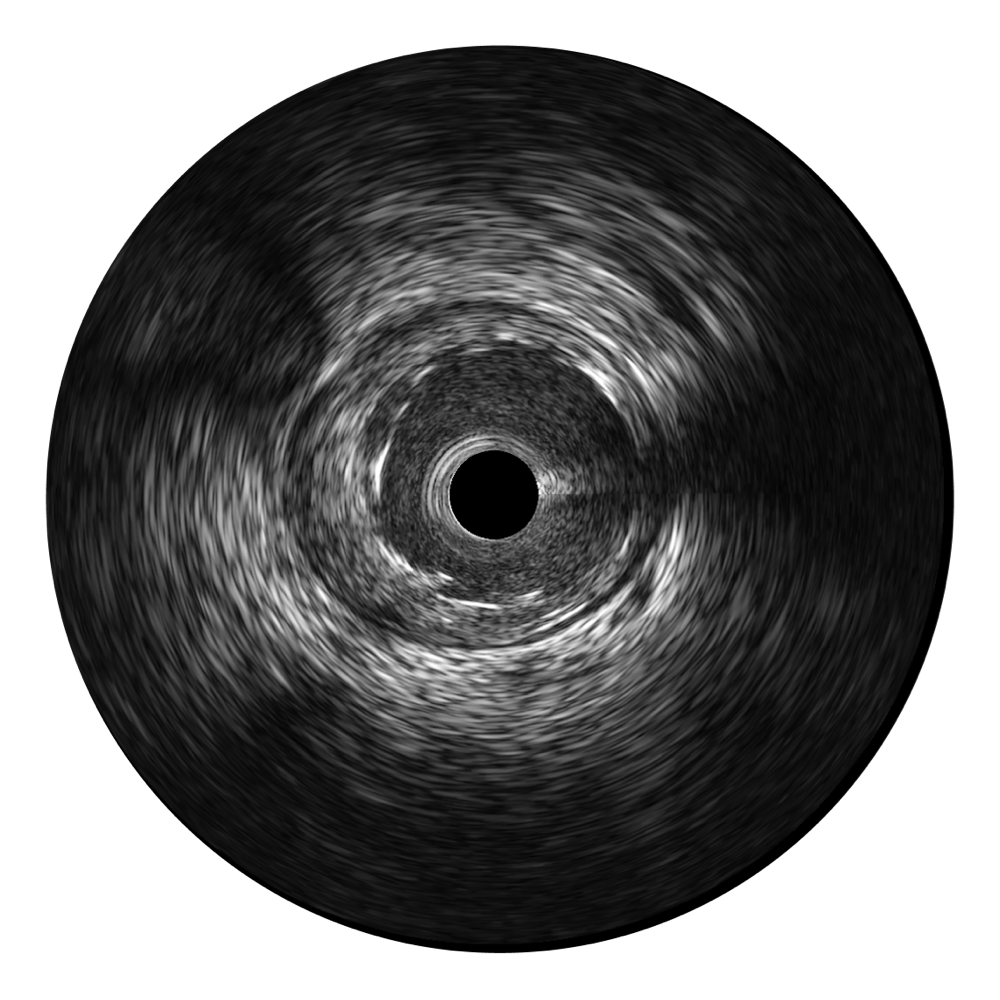

• 美狮贵宾会官网宽频IVUS图像

• 传统IVUS图像

对比传统IVUS导管成像,美狮贵宾会官网宽频IVUS图像的近场支架梁显影更细腻,远场中膜外血管仍清晰可辨,兼顾远中近,兼顾分辨力与穿透深度